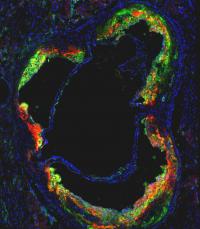

Mount Sinai's novel HDL nanoparticle (red), loaded with a statin drug, specifically targets and locally treats inflammatory macrophage cells (green) hiding inside high-risk plaque within blood vessels.